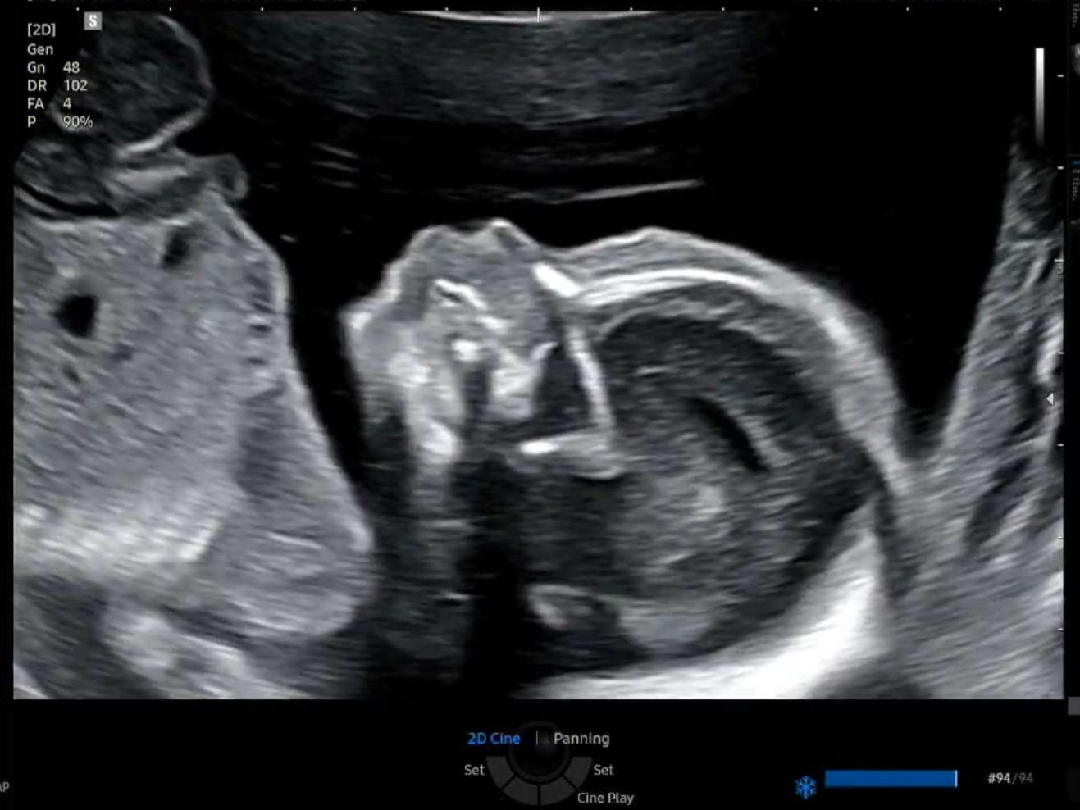

20주 정밀초음파 보고 출산일 잡고 왔어요

초기에는 그렇게 시간이 안 가더니 태동느끼고 나니까 시간이 훅훅 가네요. 출산일까지 잡으니까 아가 볼 날이 더 가까운 것 같아요. 옆모습도 야무지게 보고 왔습니다ㅋㅋㅋㅋ 다음 방문에는 3D입체 초음파 본다고 해서 기대하고 있어요.